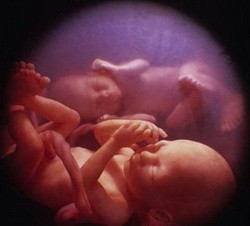

Сыновья пьющих женщин могут родиться бесплоднымиДатские ученые утверждают: даже минимальное количество алкоголя, принимаемого женщиной во время беременности, отразится впоследствии на качестве спермы ее малыша.

Чтобы прийти к такому заключению, ученым из Университета Орхауса потребовался 21 год. Сначала они изучили медкарты 12 000 женщин, чей срок беременности составил 36 недель. По прошествии 20 лет исследователи попросили повзрослевших юношей сдать анализ на качество спермы. Принять участие в эксперименте согласились 350 человек.

Как выяснилось позже, в семенной жидкости у молодых людей, чьи матери не отказывали себе в удовольствии выпить, сперматозоидов было в 3 раза меньше, чем у их сверстников, родители которых в период беременности не употребляли алкоголь. Правда, стоит отметить, что образ жизни, который вели все эти годы молодые люди, ученые в расчет не брали.